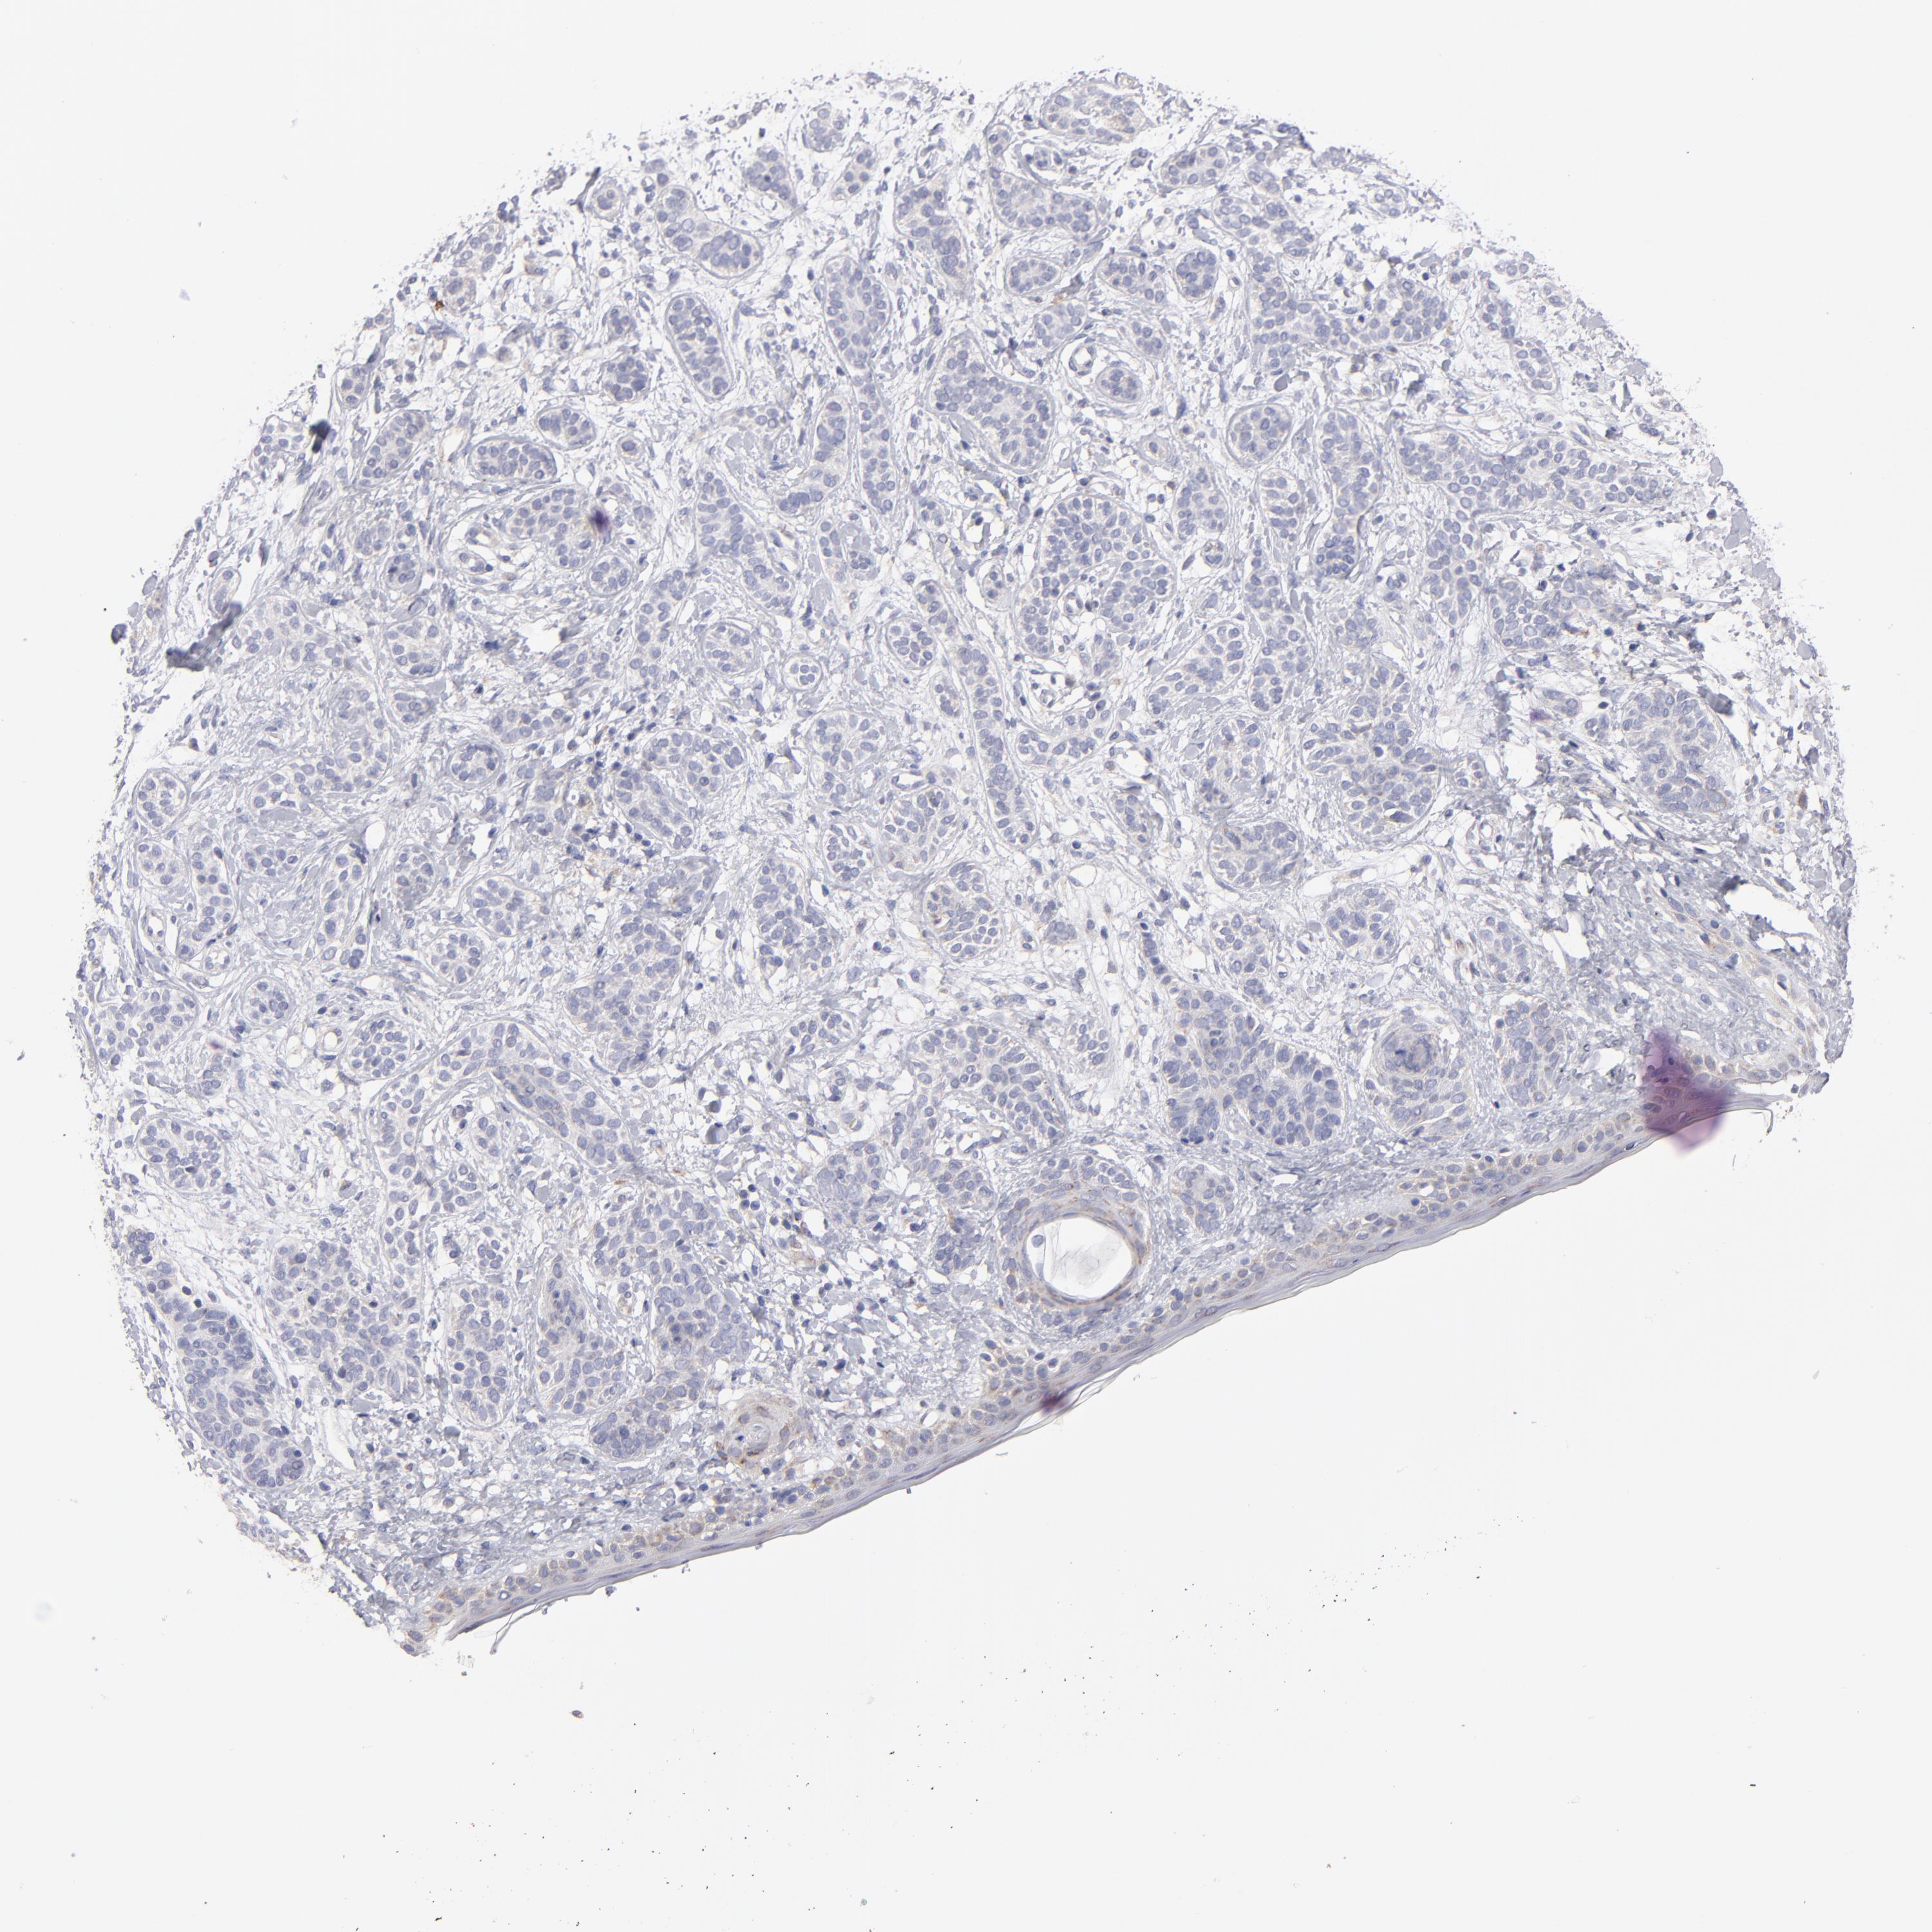

SKIN CANCER - Protein expressioni

A mouse-over function shows sample information and annotation data. Click on an image to view it in a full screen mode. Samples can be filtered based on level of antibody staining by selecting one or several of the following categories: high, medium, low and not detected. The assay and annotation is described here.

Antibody stainingi

Antibody staining in the annotated cell types in the current human tissue is reported as not detected, low, medium, or high, based on conventional immunohistochemistry profiling in selected tissues. This score is based on the combination of the staining intensity and fraction of stained cells.

Each image is clickable and will lead to virtual microscopy that enables deeper exploration of all samples and also displays staining intensity scores, fraction scores and subcellular localization as well as patient and tissue information for each sample.

Antibody HPA002946

Staining

Not detected

Negative

None

Squamous cell carcinoma, NOS